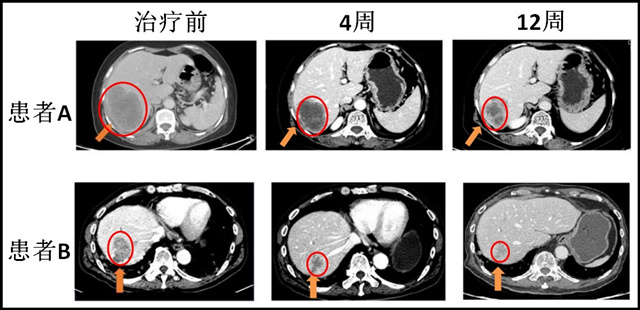

(患者使用艾维替尼AC0010治疗前后的对比)

两位患者肿瘤都明显缩小了30%以上。

这两位患者都是使用一代 EGFR 抑制剂大约2~4年以后,出现耐药性,基因检测确认有 T790M 突变。